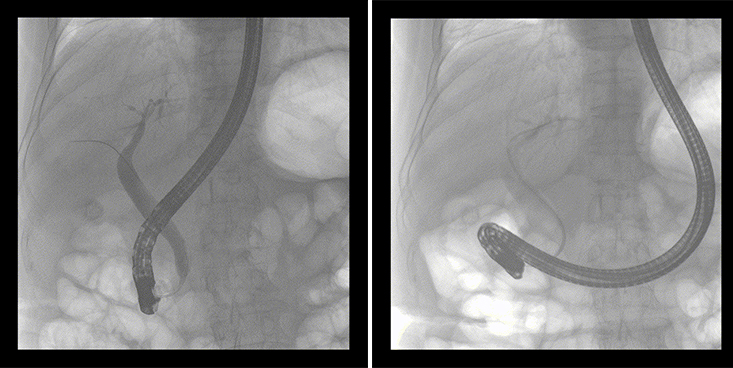

移動式平板中C術中影像

普愛醫(yī)療移動式平板中C為本次ERCP手術提供實時無損高清影像,幫助醫(yī)生精準定位?!俺上裥Ч浅0簦⊥耆惠攪H大牌的醫(yī)學影像設備……”鼓樓醫(yī)院江北國際醫(yī)院內鏡中心手術團隊對普愛醫(yī)療移動式平板中C的成像效果給與了高度的評價。

一位86歲的女性患者近來出現腹痛,入院后CT檢查并結合臨床表現被診斷為急性膽囊炎伴膽囊結石。經專家團隊協商并與患者家屬溝通,決定對患者實施經內窺鏡逆行胰膽管造影(ERCP)。

ERCP(經十二指腸鏡下逆行胰膽管造影)現已成為比較成熟的微創(chuàng)介入技術,被廣泛的應用于臨床,ERCP也是消化內鏡領域難度大、風險大、技術復雜的微創(chuàng)手術,其并發(fā)癥多為致命性,ERCP手術對醫(yī)生的要求很高,因此,ERCP醫(yī)生又被稱為“刀尖上的舞者”。因為手術難度較大,過程復雜,需要C形臂精準的配合,對影像清晰度的要求也非常高。